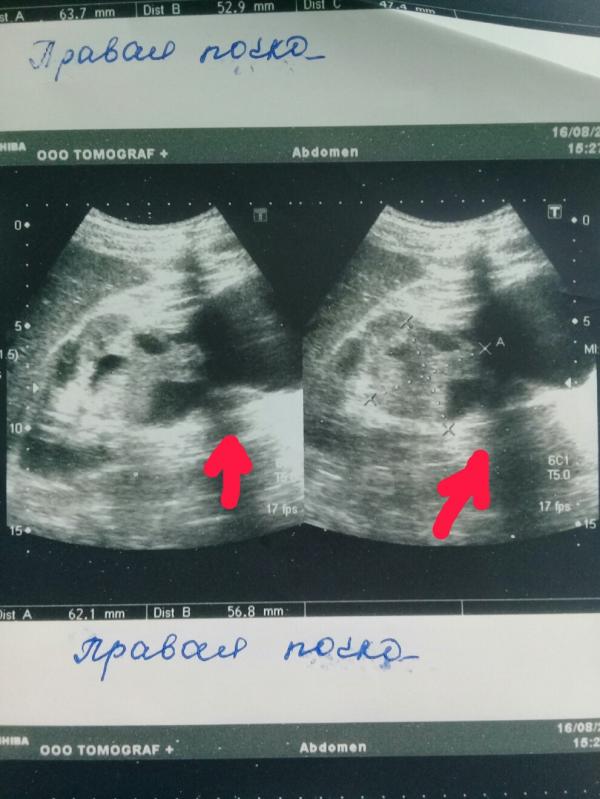

Только в машине я прочитала заключение-ЗНО правой почки. Полезла в интернет, набираю в поисковике ЗНО.... И....все- мой мир рухнул-ЗЛОКАЧЕСТВЕННОЕ НОВООБРАЗОВАНИЕ ПРАВОЙ ПОЧКИ.